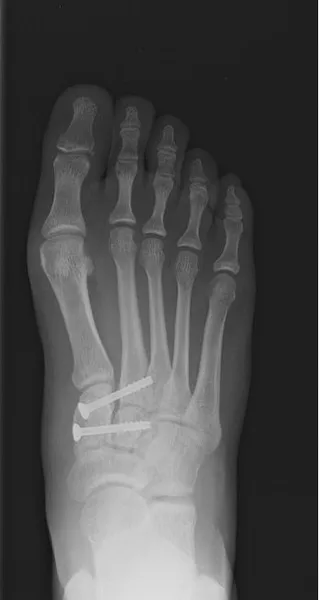

Below is the case of a young female athlete was injured while playing soccer, she had pain and swelling at the midfoot. MRI imaging confirmed ligament rupture. The procedure was done percutaneously with flourscopic guidance. Pictured on the left is pre operative and post operative x-ray to the right. She went on to heal uneventfully after physical therapy, and has since returned to playing soccer.

This is an example of an injury to the arch of the foot involving the Lis Franc's ligament between the base of the 2nd metatarsal and the medial cuneiform bone. This is a very important stabilizing ligament of the foot (left). This injury is repaired surgically with screws, pins and occasionally surgical plates. This case was corrected with a combination of screw and pins (right).

The images below demonstrate Lis Franc's ligament rupture with increased spacing between the medial cuneiform and the intermediate cuneiform. The ligament is attached between the base of the 2nd metatarsal and the lateral aspect of the medial cuneiform (left). The post-surgical repair with screw fixation (right) shows reduction in that aforementioned space between the cuneiforms re-establishing the stability of the medial midfoot.